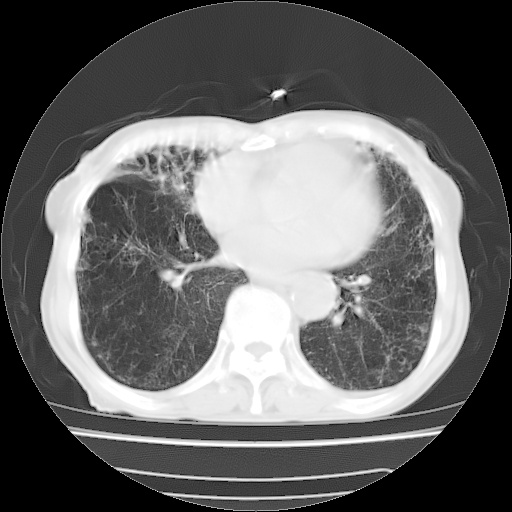

病人发热、气促就诊。原二周前已行ct扫描,当时诊断为双肺下叶、右肺中叶支气管扩张并感染,双肺上叶片状渗出性病变。今天复查胸部ct,双肺下叶支气管扩张并感染病灶较前明显吸收,但双肺上叶渗出性病变较范围较前明显增大。

现传今天ct图像给大家讨论。

肺内广泛感染并间质纤维化,牵拉性支气管扩张

双肺多发大片状、斑片状高密度渗出影,部分实变,考虑病毒性肺炎。